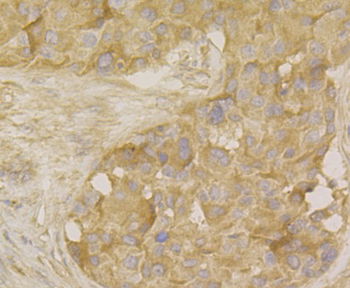

100 μl, 50 μl, 200 μl - HSC70 Mouse Monoclonal Antibody [orb704174]Featured

IF, IHC-Fr, IHC-P, WB

Human, Mouse, Rat

Mouse, Rat

Mouse

Monoclonal

Unconjugated

100 μl, 50 μl, 200 μl - ATF4 Recombinant Rabbit Monoclonal Antibody [orb704304]Featured